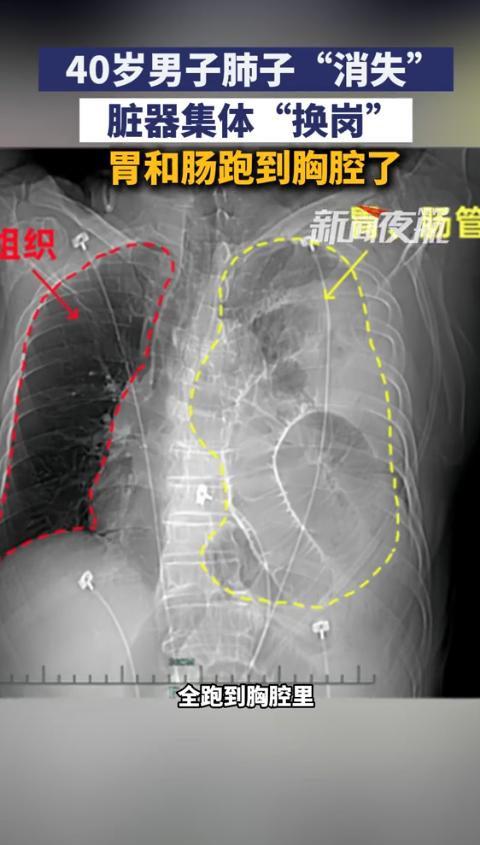

“这就是命!”浙江,一男子参加活动抽奖,意外中奖获得了一次免费体检的资格,可体检过后却发现左肺消失了,去医院检查后确诊左肺是胃和肠管移位压缩了左肺,幸运的是,这次体检提前帮他找到了问题。网友:这比中五百万还有用!   浙江一位40岁的壮年男子季哥,怎么也想不到一场随手参与的抽奖,会变成改变人生的“生死考验”。   他凭借运气抽中社区公益活动的免费体检名额,本是抱着“反正不花钱,查完图个安心”的心态前往,却在胸部CT检查后收到了让医生都神色凝重的结果。   他的左肺,在影像上几乎“消失”了。   季哥平时身体硬朗,爬五六层楼梯不喘大气,连感冒都很少找上门,更是没进过医院的大门。   拿到体检报告时,他反复揉着眼睛确认,屏幕上右侧肺部的红色影像清晰完整。   而左侧本该是肺叶的区域,却被一团不规则的阴影填满,完全看不到正常肺组织的形态。   是不是机器出问题了?我好好的怎么会少个肺?带着满肚子的疑惑和慌乱,他当天就带着报告赶往浙江大学医学院附属第一医院,直奔胃肠外科寻求答案。   接诊的副主任医师钱家杰仔细查看了CT影像后,用一个直白又形象的解释解开了季哥的困惑。   你的胸腔和腹腔之间,隔了一层叫膈肌的肌肉,就像家里复式房的‘楼板’,而你这层‘楼板’刚好破了个洞。   钱家杰进一步说明,腹腔内的压力天生比胸腔高,一旦膈肌出现破损,原本该待在腹腔里的胃和肠管,就会被压力推着向上“跑”,硬生生挤入了胸腔。   这些脏器在胸腔里不断扩张,慢慢抢占了左肺的生存空间,把脆弱的肺叶越压越小,最终在CT影像上呈现出“消失”的假象。   让季哥费解的是,这么严重的问题,自己怎么一点感觉都没有?   钱家杰解释,这和他的年龄、病情发展速度密切相关。   季哥的膈疝形成时间不算太久,加上他正值壮年,脏器功能代偿能力强,身体暂时适应了这种异常状态,才没有出现明显的不适。   但这并不意味着风险不存在,反而像一颗隐藏的“定时炸弹”:随着时间推移,左肺会持续被压迫,逐渐丧失呼吸功能,严重时可能引发肺实变、纤维化。   移位的胃肠会出现蠕动变慢、贲门松弛的问题,导致反复反酸烧心,极端情况下还可能发生肠扭转、坏死,甚至会挤压心脏,影响血液循环,危及生命。   了解到病情的严重性后,季哥当即决定接受手术治疗。   钱家杰团队迅速为他制定了腹腔镜下膈肌修补术的方案,这种微创手术创伤小、恢复快,能最大程度减少对身体的影响。   手术中,医生通过几个微小的切口伸入器械,先小心翼翼地将“跑错地方”的胃和肠管轻柔复位,送回腹腔原本的位置。   再用高强度的医用缝线将膈肌的破洞逐层严密缝合,最后铺上一张专用补片进行加固,从根源上防止破损再次发生。   整个手术过程十分顺利,术后第三天,季哥复查胸部CT时,终于看到了让他安心的画面。   被压迫已久的左肺重新舒展开来,体积恢复到正常大小,右肺也摆脱了之前的挤压,回归了原本的位置。   季哥感慨,感觉胸口一下子敞亮了,呼吸都比以前顺畅太多,就像卸下了一个看不见的包袱。   若不是这次意外的体检,他根本不知道身体里藏着这么大的隐患,这次抽奖抽来的不是体检,而是“第二次生命”。   季哥的经历被分享到网络后,迅速引发了网友的热烈讨论。   有网友留言,这哪是中了体检,分明是中了‘救命符’,比中五百万还珍贵。   这场意外的“幸运”,也让很多人重新审视“幸运”的真正含义。   生活中没有那么多“刚好中奖”的巧合,却有无数“主动关注健康”的机会。   我们总以为疾病离自己很远,却忘了它可能正潜伏在身体的某个角落,等待着被忽视的机会。   健康从不是理所当然的馈赠,而是需要一生用心呵护的宝贵财富。   一次常规体检、一个良好的生活习惯、一份对身体信号的敏感,都是守护健康的坚固屏障。